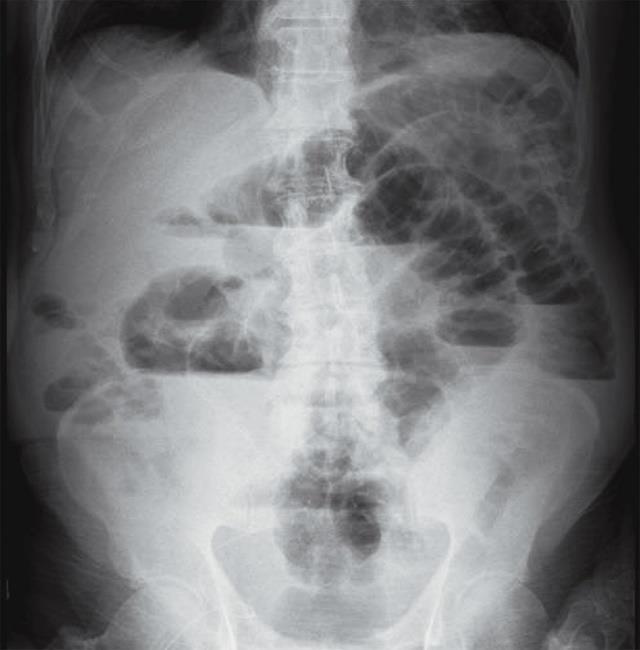

Setratadepacientemasculinode71años de edad originario de la Mixteca, Oaxaca, sin antecedentes patológicos de importancia, quien iniciamesesprevios,condificultadparaevacuar, distensión abdominal progresiva, así como dificultadparaexpulsargases,dichossíntomasse exacerban 72 horas antes previo a su internamiento, así mismo se acompaña de pérdidaponderalde6kilosaproximadamenteen los últimos 6 meses que no recibe tratamiento

médico, porloqueacudealserviciodeurgencias denuestraunidad,donderealizanunaradiografía deabdomen,dondesemuestrauncolondilatado, con engrosamiento de ileón distal, así como elevación de hemidiafragma izquierdo (Figura 1). A la exploración física se observa paciente pálido,caquéctico,conabdomendistendido ya laauscultaciónconhiperistaltismointestinal.La biometría hemática realizada muestra Hemoglobinade10g/dLyHematocritode32%, acompañadodeligeraLeucocitosis.Porloquees intervenido quirúrgicamente con diagnóstico presuntivo de Neoplasia intestinal. En la intervención quirúrgica se observa un colon dilatado, con válvula ileocecal prominente, con presencia de induración de ileón terminal (Figura2),elestudiohistopatológicomuestraun proceso ulcerativo profundo a nivel ileal, recubierto por restos celulares, células inflamatorias, fibrina y material hematoxilinico agrupadosengránulosdeaparienciafibrilar,que alteñirsecontécnicahistológicadePASdichos gránulos están constituidos por estructuras

1.

Radiografíaabdomen.Distensióndeasasintestinalesconniveleshidroaéreos.

Figura